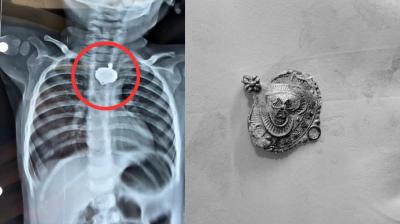

बड़वानी में 9 माह के बच्चे की आहार नली में फंसा मंगलसूत्र, डेढ़ महीने बाद एक्स-रे से खुलासा

24 Nov, 2025 08:30 AM IST | BNNTIMES.IN

बड़वानी: रविवार को जिला अस्पताल में एक बेहद संवेदनशील और हैरान करने वाला मामला सामने आया. जब 9 माह के एक बच्चे के गले में मंगलसूत्र फंसा हुआ देखा गया. घटना...